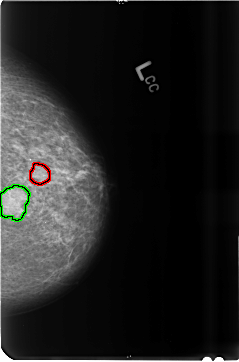

B_3515_1.LEFT_CC

FILE: B_3515_1.LEFT_CC.OVERLAY

TOTAL_ABNORMALITIES 2

ABNORMALITY 1

LESION_TYPE MASS SHAPE ROUND-OVAL MARGINS CIRCUMSCRIBED-OBSCURED

ASSESSMENT 4

SUBTLETY 5

PATHOLOGY BENIGN

TOTAL_OUTLINES 1

BOUNDARY

ABNORMALITY 2